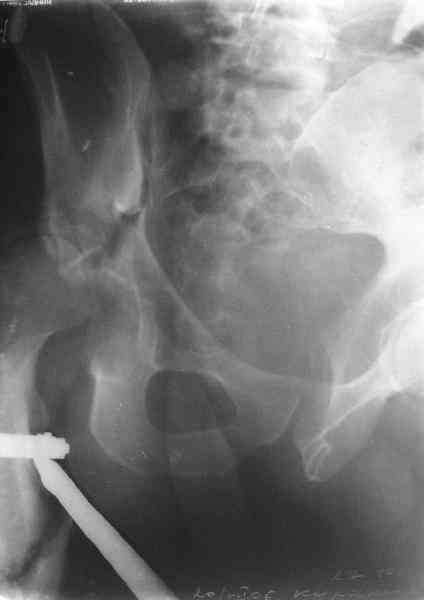

Now, to my own opinion. I believe that this is a Transverse + Posterior wall fracture type.

The transverse element does not seem so much displaced, and now after 1 month I believe it will be extremely difficult to mobilize and reduce. So I suggest you get a CT to check for incarcerated fragments, a high possibility in this unreduced dislocation. Then you open posteriorly, Kocher Langenbeck, with the patient prone, extract any incarcerated frgments, reduce the hip, fix the posterior wall by screws, and then apply a contoured reconstruction plate from the iliac wing to the ischium. This plate will hold the ransverse element, as well as buttress the posterior wall fragment(s).